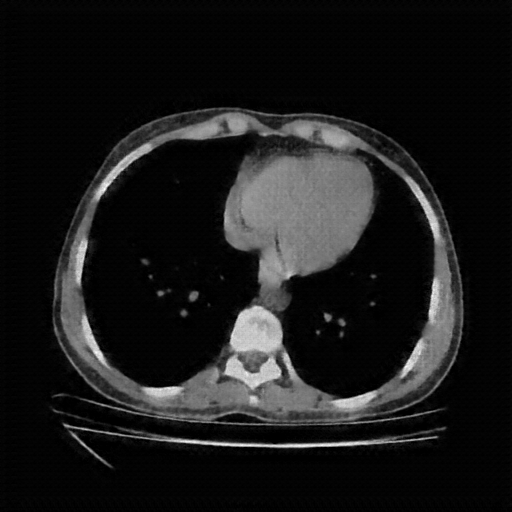

Generated VENOUS CT scan (A→B translation)

Full window (WL 1023.5, WW 4095 β†’ Low βˆ’1024, High +3071)

Actual HU range: [-1024.0, 885.5]

Lung window (WL -600, WW 1500 β†’ Low βˆ’1350, High +150)

Actual HU range: [-1200.6, 150.0]

Mediastinum window (WL 40, WW 400 β†’ Low βˆ’160, High +240)

Actual HU range: [-160.0, 240.0]